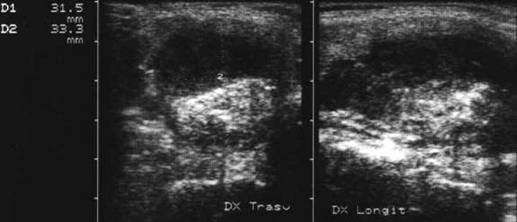

Lob drept , proiectie longitudinala si trasversala .

Barbat de 44 ani. Nodul mare in lobul drept si istm de 31x44x44mm, (30 cc) cu contur net, hipoecogen, neomogen, cu macrocalcificare.

Examn citologic: neoplazie oncocitara (a c. Hurthle).

Examen histologic postoperator: adenom cu celule Hurthle.